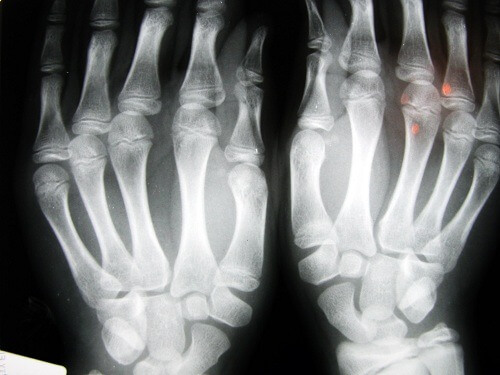

Hvad der blev opdaget under denne undersøgelse var, at fingrene viste tegn på skade, såsom ledbåndsskader og en nedsat evne til at holde fast i ting. Dette synes at være relateret til den hurtige og gentagne strækning og kontrahering af ledbåndene.

Vi ønsker ofte at lindre smerter eller sammentrækninger med denne bevægelse. Men vi bør også huske på, at det for vores led er noget pludseligt, unaturligt og ikke særlig hensigtsfuldt. Og i modstrid med den gængse opfattelse, så mindsker det ikke muskelspændinger. Men resulterer snarere i tab af mere synovialvæske, det naturlige smøremiddel, som forhindrer friktionen mellem knoglerne. Dette kan føre til nedbrydning af leddene, men også øge sandsynligheden for fraktur eller brækkede knogler. Andre konsekvenser er stivhed, deformation af det skadede område, og stærk smerte der går væk ved hvile.

Dem der lider mest af dette problem, er voksne over 40 år. Og de områder hvor at knække leddene resultater i den største nedbrydning, er i hænderne (fingre og håndled) og i nakken. Den bedste måde at undgå dette problem er ved at motionere, under hensyntagen til vores alder og fysiske tilstand. Gåture og svømning er de mest anbefalede former for motion.

Et andet studie undersøgte 30 ældre mennesker på et plejehjem i Los Angeles. Dem der havde knækket deres knoer hele livet havde ikke slidgigt. I en tredje undersøgelse, denne gang med voksne på 45 år fra Detroit, blev det opdaget. At det største problem var tab af styrke i deres greb, og også at over 80% af de undersøgte led af hævelse i hænderne.